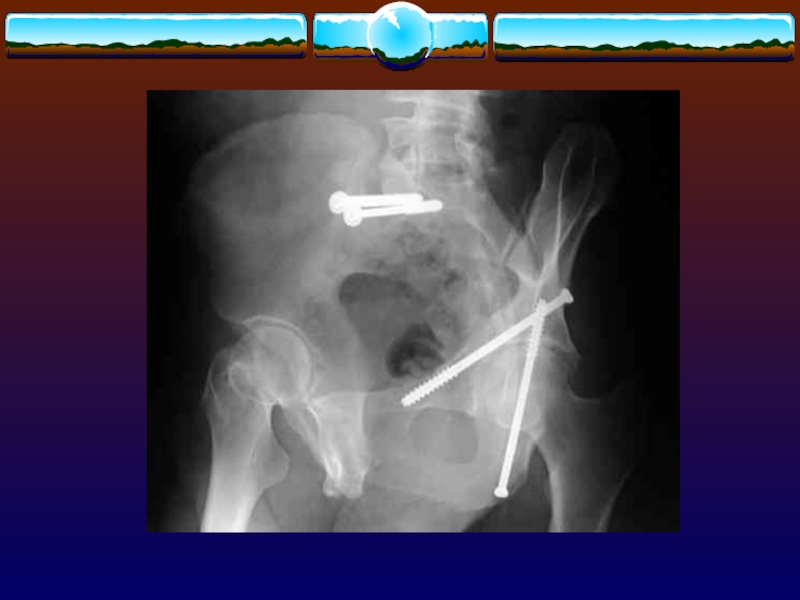

Слайд 74Перелом типа 61А

Перелом типа 61А